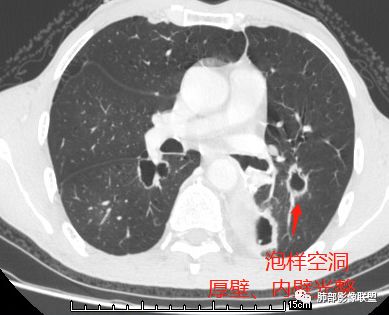

(1)囊样空洞, 呈圆形或类圆形, 直径>15 mm,壁薄 (1 ~ 2 mm)而均匀 ,内壁欠光整 ;

(2)小环形空洞 ,呈圆形 ,壁薄 (2 ~ 4 mm)而均匀 ,直径≤15 mm, 内壁光整;

(3)泡样空洞, 呈圆形或类圆形 ,壁厚 ( >4 mm),内壁光整;

(4)不规则空洞, 洞腔形态不规则, 壁厚 ( >4 mm)且不均匀, 内壁不光整;

其中囊样空洞和小环形空洞属于薄壁空洞,泡样空洞和不规则空洞属于厚壁空洞,其中腺癌空洞型肺转移瘤主要表现为小环形空洞,以下3个病例均表现为小环形空洞的转移瘤: